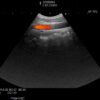

Hitachi C42T Ref Intraoperative Convex – ARIETTA

ARIETTA Convex C42T Intraoperative

Intraoperative Finger-grip T-Style

Frequency Range

10 – 3 MHz

Hitachi C42T Intraoperative Convex – ARIETTA

Frequency Range: 10 – 3 MHz

Scan Width: 20 mm Radius

Scan Angle: 65° FOV

Hitachi C42T Intraoperative Convex – ARIETTA for Intraoperative Finger-grip Convex T-Style

Compatible with Hitachi Arietta Systems